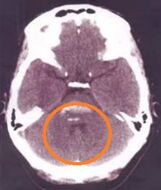

74.44歲女性有酗酒習慣,某日熬夜喝酒之後突然口語不清,吞嚥困難,因此被送到急診求治;患者未注射對比劑的電腦斷層掃描檢查如圖,最可能的診斷為何?

Hyperdense出血性

Hypodense缺血性

可以看到腦幹的部分是hyperdense